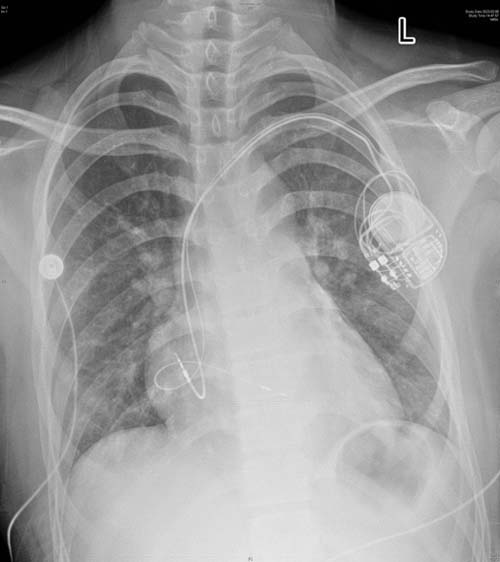

On February 7, Professor Han Bo, Director of Pediatrics and Director of Department of Pediatric Cardiology at Shandong Provincial Hospital Affiliated to Shandong First Medical University (Shandong Provincial Hospital), led the team successfully implant the first case of a 3.0T dual-chamber anti-nuclear magnetic permanent pacemaker with left bundle branch pacing in Shandong Province for a 13-year-old child.

The child was found to has cardiac dilatation with complete left bundle branch block upon birth, and developed into grade III atrioventricular block 7 years ago, with a 24-hour average heart rate of 41 beats/min and a significantly enlarged left ventricle, urgently needing implantation of a permanent cardiac pacemaker. On the afternoon of February 6, all medical staff in the Department of Pediatric Cardiology held pre-operative discussions and made adequate preoperative preparations for the child. On the morning of February 7, Professor Han Bo successfully performed the surgery on the child in the Interventional Diagnosis and Treatment Center, using the left bundle branch pacing, which is more in line with the child’s physiological characteristics. After test, the pacemaker functioned well, and the child returned to the ward safely.

Left bundle branch pacing is a new pacing technique created by the Chinese scholar Professor Huang Weijian in 2017. This technique is to rotate the ventricular pacing electrode through the right interventricular septum side to the left interventricular septum side under the endocardium via vein. During pacing, the left bundle branch area can be captured to quickly excite the ventricular muscle to ensur the synchronous contraction of the left ventricle. is guaranteed,and the pacing QRS wave is narrow. and the locally abundant myocardium provides safe backup pacing, so that the pacing parameters are superior for safety and stability in the long term. This approach can correct left bundle branch block. In addition to cardiac pacing function, using a dual-chamber anti-nuclear magnetic pacemaker and left bundle branch pacing technology is also beneficial to improving cardiac function, benefiting the child a lot.